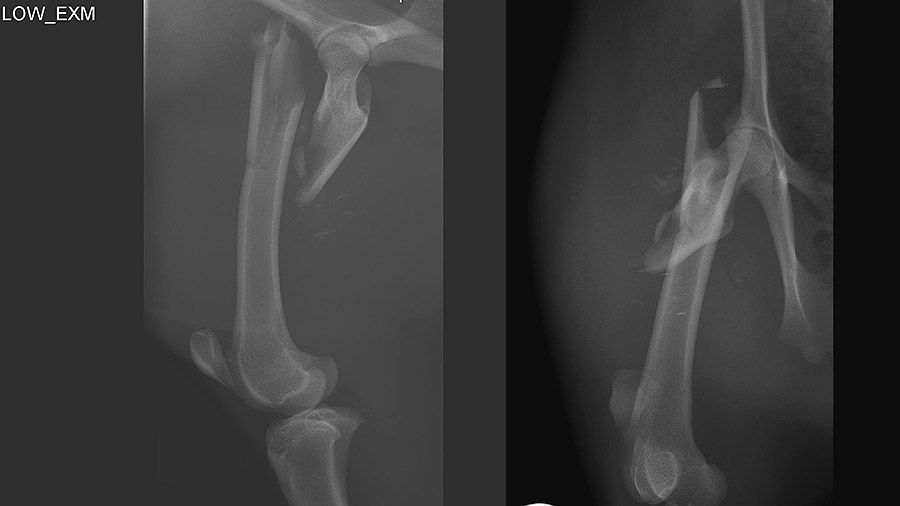

Officials at the Zoo Halle had approached Jopp with an X-ray of Esta’s injury.

“Even getting the x-ray was no easy task, either,” she added. Because pudus are such shy, skittish and solitary animals, they tend to bolt when approached, so her caregivers at the zoo used a dart gun to tranquilize her for the x-ray process.

“The x-rays showed that it was a rather complicated fracture, around two weeks old. She was lame and in pain—and these are animals that have to run. Because they are so easily frightened, it is their nature to run away,” Jopp said, adding that a return to full function was key to ensuring the animal’s quality of life.

Complicating the case was a range of factors: Esta’s pregnancy, a lack of scientific literature on pudu anatomy, and the fact that pudus are ruminant animals requiring extra caution when they are sedated for surgery. So the pressure was on when Esta arrived in the operating room.